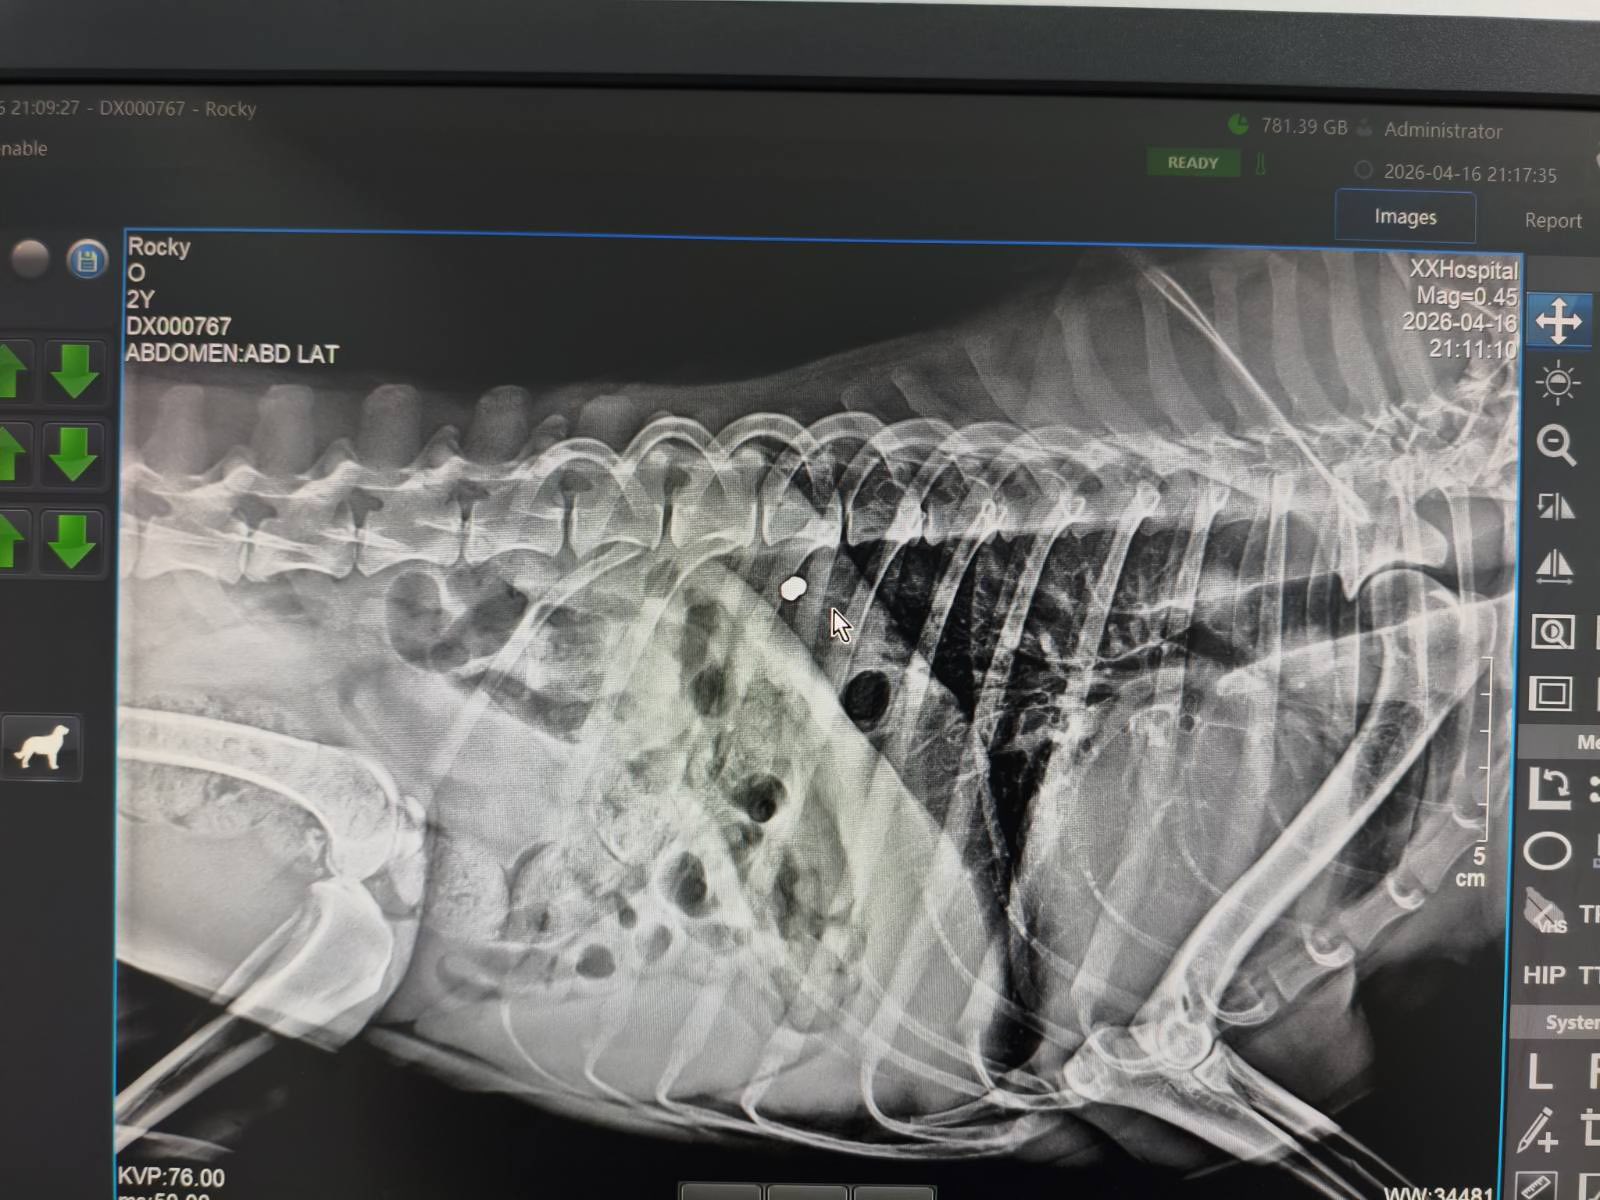

Υπενθυμίζεται ότι στις 22/04/2026 πυροβολήθηκε η Μαΐλη, ενώ, σύμφωνα με νεώτερες πληροφορίες, είχε προηγηθεί στις 10/ 04/2026 ο πυροβολισμός του σκύλου Rocky στην ίδια περιοχή. Ο Rocky μεταφέρθηκε σε κτηνίατρο όπου αναρρώνει και θα υποβληθεί σε εγχείρηση για αφαίρεση σφαιριδίου.